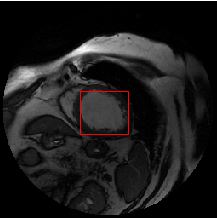

The Figure 1 below shows an example of an input image, the inferred region of interest (ROI), corresponding to the manually delineated contours.

From one original MRI image and its corresponding contour (provided as a list of coordinates of every point of the contour), we have to compute binary masks. We use the previous as inputs to our combined approach. An example is shown in Figure 2.